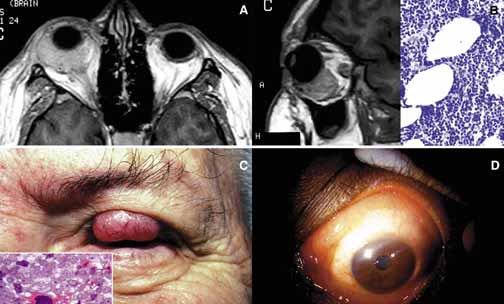

Cavernous hemangioma is another benign vascular tumor that occurs in adults, usually as a solitary, unilateral lesion, but multiple tumors have been described.185,186 Unlike capillary hemangioma it is not associated with other lesions elsewhere in the body. It is usually located within the muscle cone but may also be seen in extraconal locations and presents with slowly progressive proptosis without too much extraocular motility disturbance (Fig. 18). Gross appearance of cavernous hemangioma is a well encapsulated reddish purple lesion with a sponge-like consistency on its cut surface. Histopathologically, it consists of dilated vascular channels lined by endothelium and smooth muscle and intervening fibrous stroma. The endothelial cells are held together by tight junctions and display basement membrane reduction. Clinical differential diagnosis of cavernous hemangioma on imaging include fibrous histiocytoma, hemangiopericytoma, schwannoma and metastatic tumors.187 Surgical removal of the tumor is the treatment of choice.

Fig. 18 Cavernous hemangioma. Despite the presence of a large intraconal tumor in T1-weighted axial MRI, the left globe shows minimal proptosis because of the slowly growing nature of the tumor. This tumor was compressing onto the optic nerve to cause significant papilledema but the patient did not have any extraocular motility disturbance. The gross photograph of the transverse section of the well encapsulated cavernous hemangioma shows multiple loculations of the tumor. Histopathologically the Masson trichome stain demonstrates numerous caverns surrounded by thin fibrous septal, containing clusters of red blood cells. The arrow points to the capsule of the neoplasm. Note that some of the orbital fat is in fact within the fibrous tissues of the tumor (arrowheads).

Another lesion of this category that presents with large cavern formations surrounded by different amounts of fibrous tissue is lymphangioma.188–190 Unlike cavernous hemangioma, however, the space formations in this lesion are not lined by endothelial cells and do not contain vascular smooth muscle; the spaces are lined by flat mesothelial-like cells (Fig. 19). Spontaneous bleeding may take place within these cystic spaces resulting in “chocolate” cysts. In one-third of the cases, lymphoid follicles with germinal centers may be present in the intervening fibrous stroma and some tumors with abundant lymphoid tissue may respond to systemic steroid treatment. Because of the infiltrating nature of this tumor, surgery is not an early option of management; these lesions should be managed conservatively.190

Fig. 19 Lymphangioma. A 23-year-old woman with marked axial proptosis of the left eye secondary to lymphangioma (A). The tumor is depicted in the T1-weighted axial MRI showing a multiloculated tumor with marked enhancement occupying the entire orbit (B). Frame C shows multiple irregular lymphatic spaces (ls) that were changing in size and shape during the B-scan ultrasonography. The histopathology of the same case (D, E) reveals multiple lymphatic spaces (ls) lined by flat mesothelial-like cells surrounded with irregular fibroconnective tissue and lymphoid follicles with germinal centers (g). Note that some of the lymphatic spaces are filled totally or partially with blood.

Orbital varix is another orbital vascular lesion that develops as a distention of a venous channel leading to stagnant blood flow resulting in thrombus formation.191 Orbital varices are divided into primary lesions, confined to the orbit and secondary lesions associated with intraorbital and intracranial arteriovenous malformations.54 Vascular hamartomatous lesions may contain arteriovenous malformations with or without abnormal communication between arterial and venous vasculature. These lesions should not be confused with carotid cavernous and dural cavernous fistulas, which affect the orbit secondarily.192 If one clinically suspects an A-V malformation component in an orbital vascular lesion, CT angiogram and arterial and venous angiograms should be used to rule out the connection of the lesion to systemic circulation.193 Color Doppler flow imaging has also been used to examine these tumors. In addition to the above detailed vascular tumors, angiosarcoma, Kaposi sarcoma, intravascular papillary endothelial hyperplasia (IPEH), vascular leiomyoma and angiolymphoid hyperplasia with eosinophilia (Kimura disease), can rarely be encountered in the orbit.194–198

In this chapter, neural neoplasms are covered under two major groups: tumors originating from central nervous system (CNS) tissues, and tumors originating from peripheral nerves.